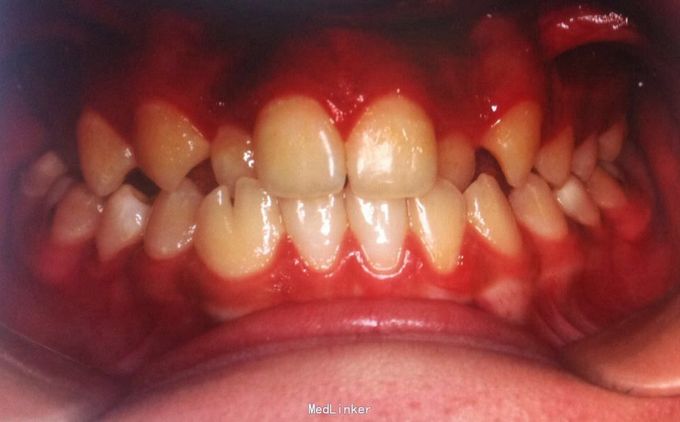

恒牙期 左右磨牙近中关系 12,22舌侧错位 32、33融合牙 右侧磨牙反合 上下牙列轻度拥挤 关节有弹响

安氏三类、后牙反合 不拔牙矫治,直丝弓矫治器,排齐整平上下牙列,解除后牙反合,矫治后覆合覆盖正常,磨牙中性关系,维持现有面型